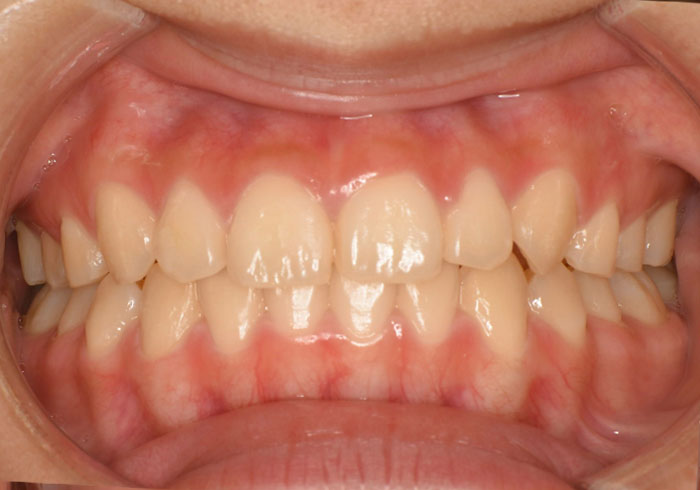

歯のガタガタ(叢生)を治療するときには前から4番目の歯を抜くことが多いですが、今回はお顔とのバランスを考慮し、親知らずのみ抜歯して治療を行いました。

治療後

マウスピース矯正 マウスピース矯正 マウスピース矯正

治療法 マウスピース矯正

主訴 前歯が出ているのが気になる。

治療期間 1年半